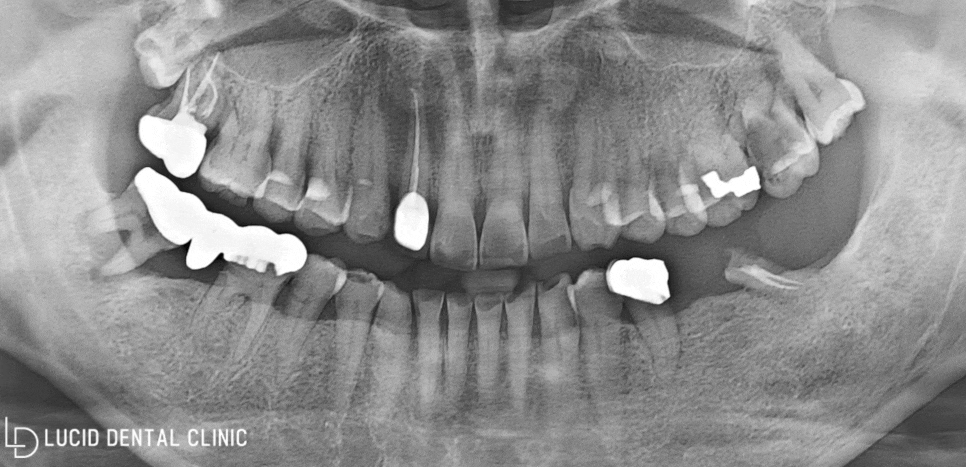

아래 보이는 것이 촬영된

파노라마 엑스레이 사진인데요

(1) 충치가 심하게 진행되어

치관(머리 부분)이 소실되거나,

(2) 신경을 넘어서까지 감염되고,

(3) 치조골 퇴행 및 치아 정출이

함께 나타난 모습을 발견했습니다.

문제점이 나타난 모든 곳이

더는 보존할 수 없을 정도라

결국, 논현동 치과 에선

발치 판정을 내렸습니다.